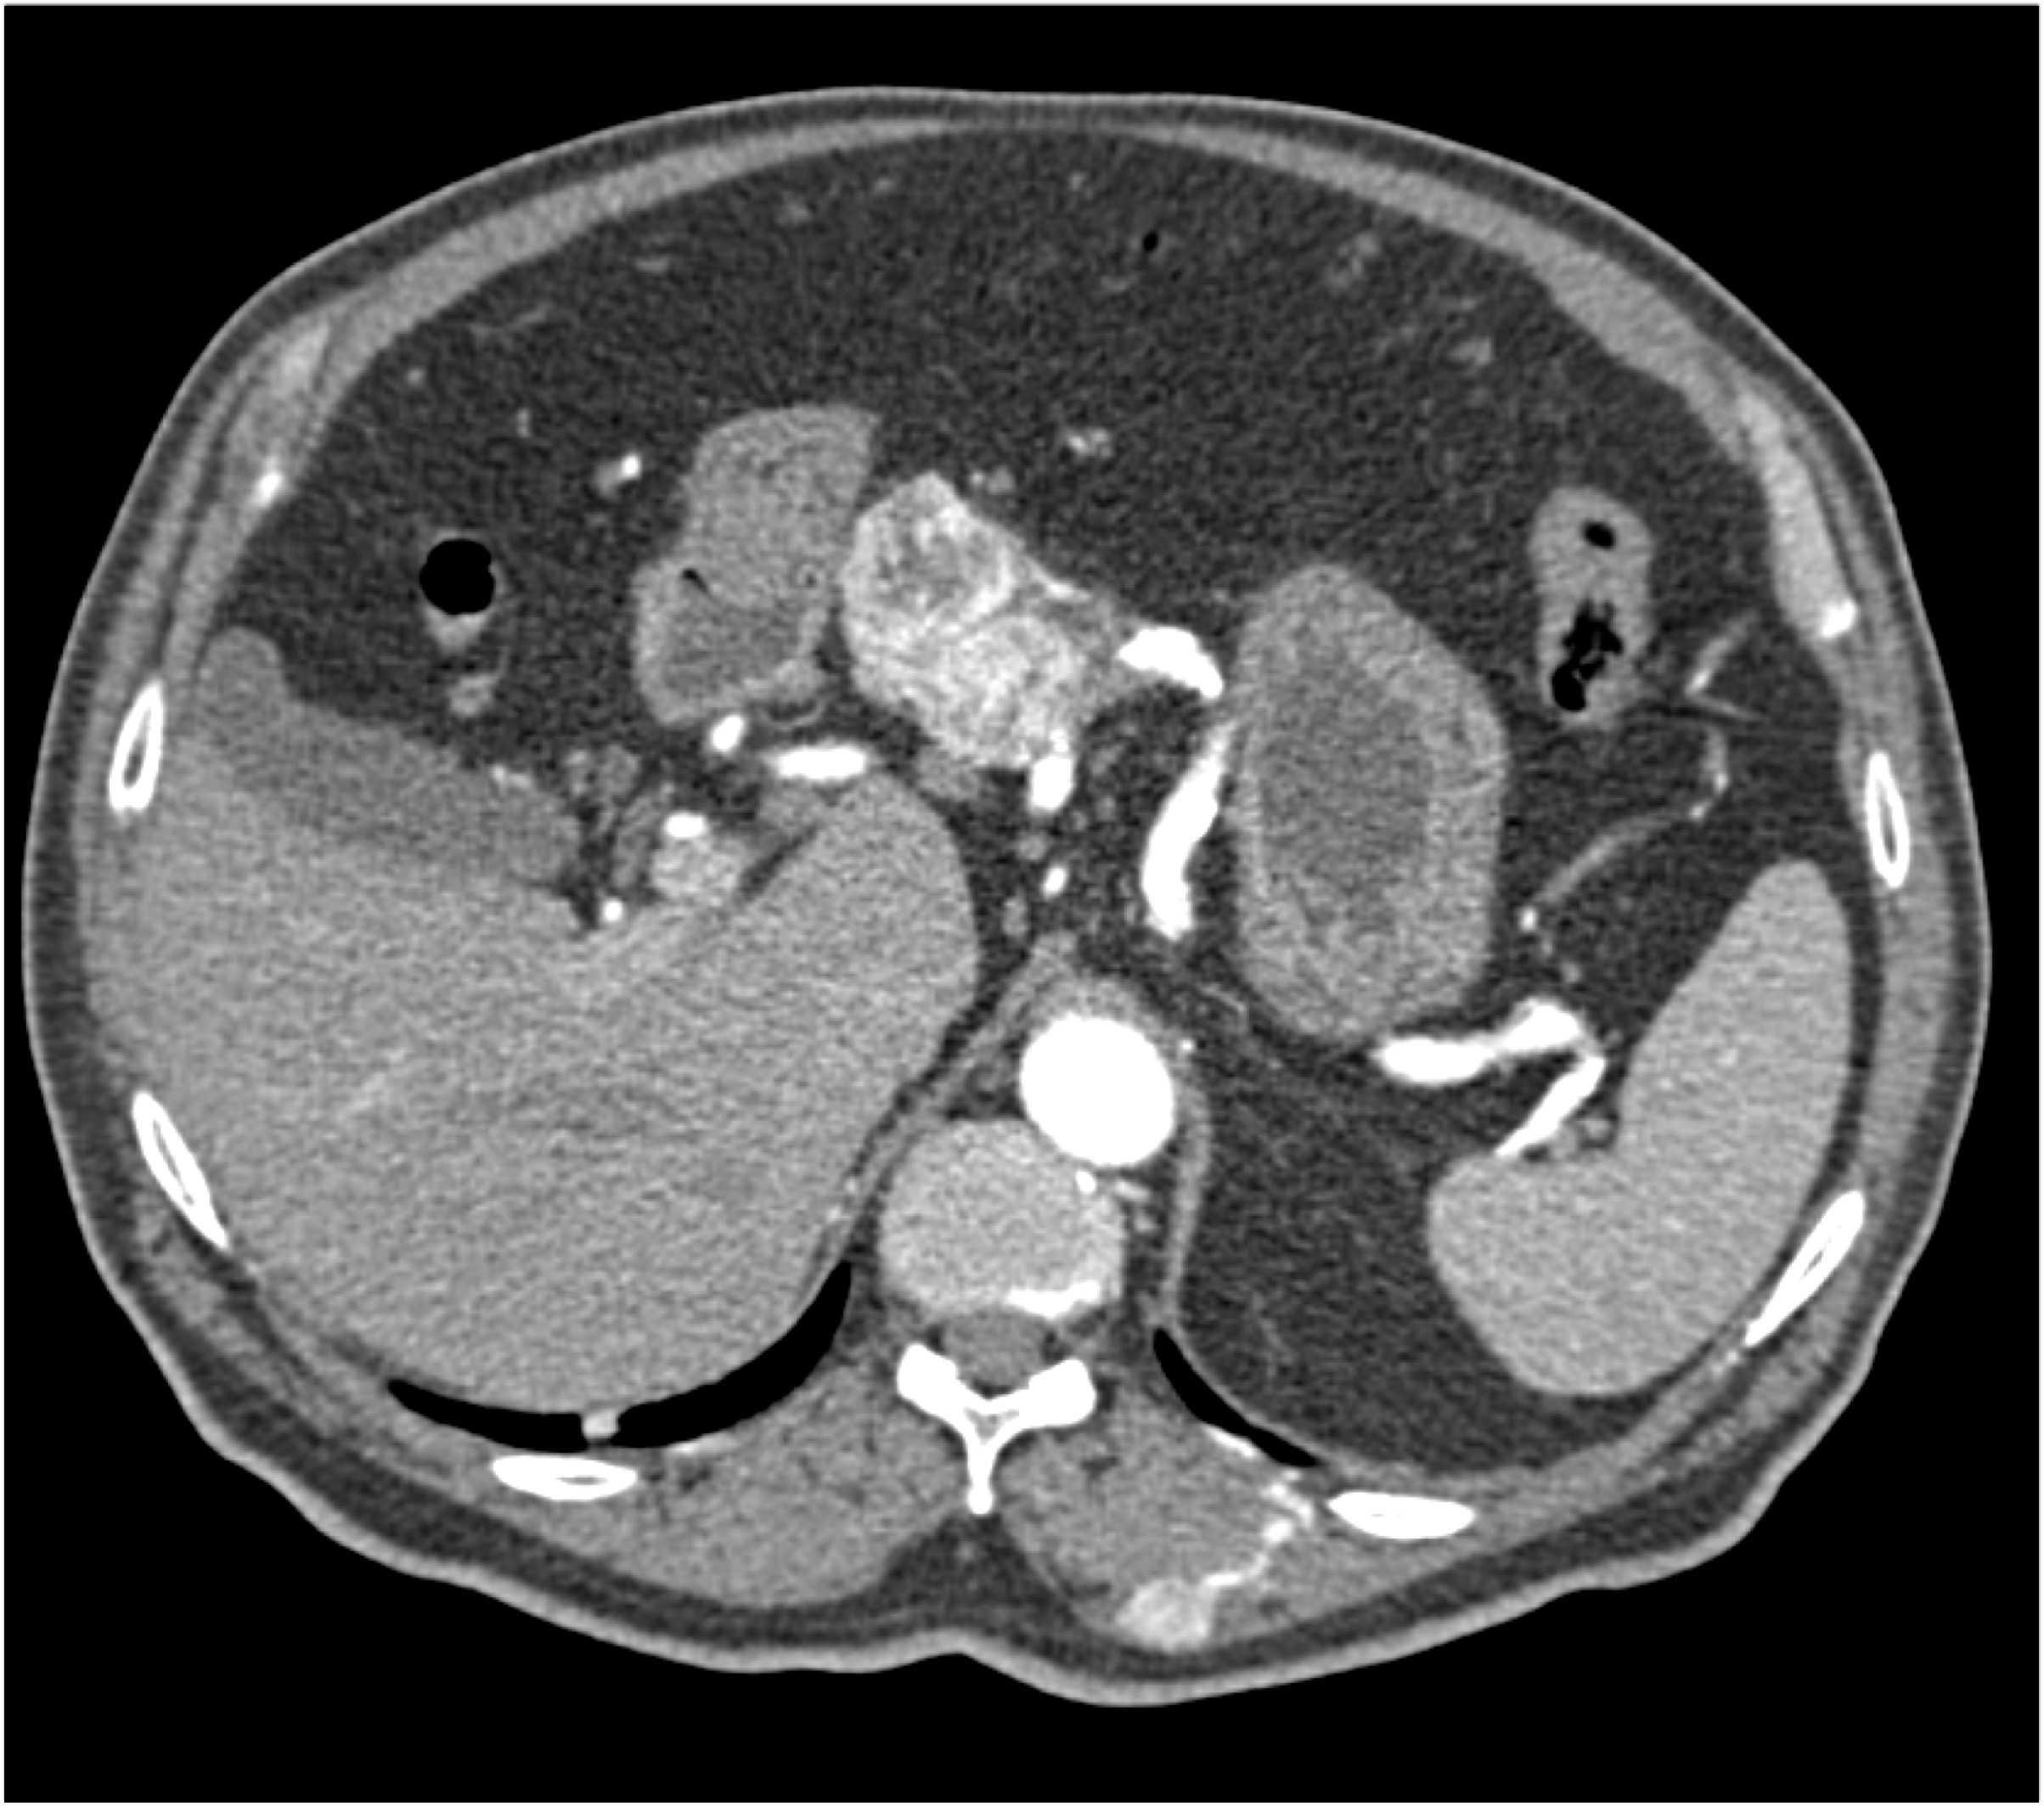

- Evaluate the CT images of each question carefully.